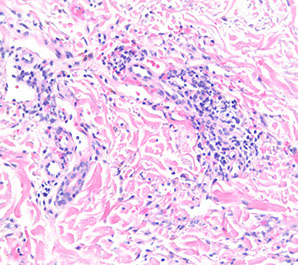

PolyArteritis Nodosa (PAN)

Immune complex-mediated transmural vasculitis c fibrinoid necrosis of small and medium muscular arteries

Micro: bx shows segmental fibrinoid necrosis of inflamed arterial walls, c a predilection for branch points

- characteristic feature is segmental nature of involvement, c active and healing lesions next to normal segments of bv's

- multiple aneurysms and constrictions on arteriogram

Polyarteritis Nodosa